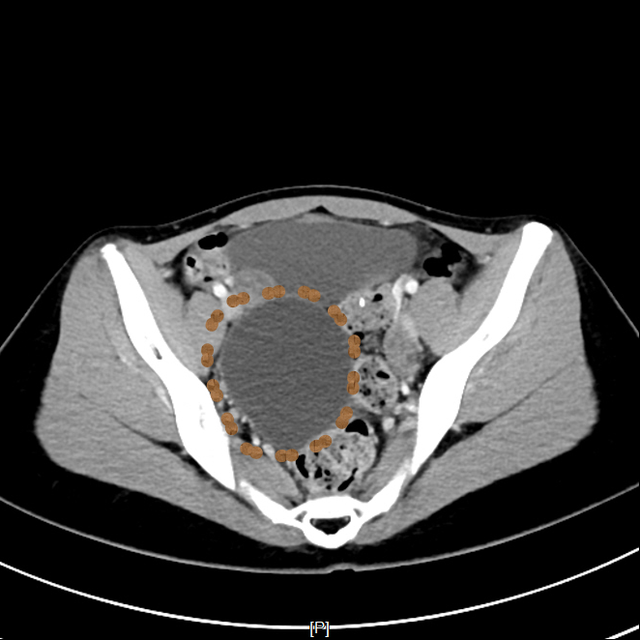

▲小黄的影像学检查

14岁女生小黄因小腹不适由母亲带至昆山市中医医院妇科就诊,超声检查后发现右附件区有一个8.0*7.2cm的巨大囊肿。由于正值初三备考的关键时期,如何解决囊肿还不能耽误复习迎考,这成了选择手术方式的关键点。

超声介入团队联合妇科对患者进行全面综合评估后,认为超声引导下抽液硬化治疗是其最佳选择。待一系列术前常规检查后,在局部浸润麻醉下进行囊肿穿刺抽液硬化治疗。

整个治疗过程顺利,患者无明显不适,未影响其正常复习迎考。三月后腹部超声检查,右附件区囊肿已完全吸收。